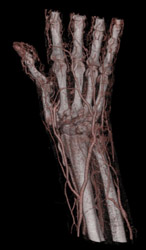

Soft Tissue Swelling